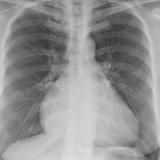

Cardiomegaly, esp RA PA

Date: 01/26/2009

Views: 2921